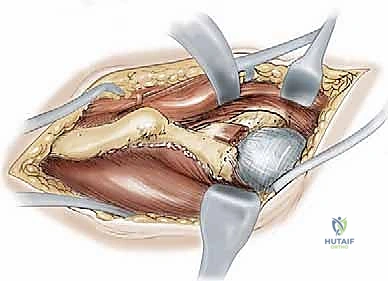

Reorientation and Definitive Fixation

Once liberated, the acetabular fragment is highly mobile. Using the Schanz pin as a joystick, the acetabulum is reoriented to achieve the preoperatively templated coverage. Typically, this involves anterior and lateral rotation (extension and abduction of the fragment) and medialization of the hip center. The fragment is temporarily held with long Kirschner wires.

Intraoperative fluoroscopy is absolutely critical at this juncture. AP, false profile, and ilio-oblique views are obtained to confirm the correction of the LCEA, normalization of the Tönnis angle, and restoration of anterior coverage without inducing iatrogenic retroversion or femoroacetabular